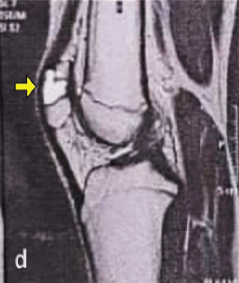

Aneurysmal Bone Cyst-cloaked Codman’s Tumor in the Patella: Case Report of an Easily Misdiagnosed Entity

D Naveen Kumar , Silambarasi Nagasamy

………………………………p.174-178